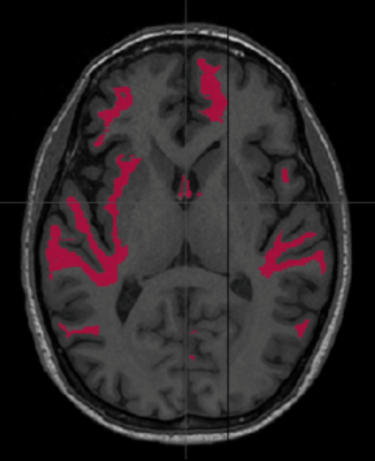

Common symptoms typically fall into three categories: physical, cognitive, and behavioural. Due to the absence of definitive biomarkers and the wide array of diagnostic criteria, clinicians often approach mTBI diagnosis through a combination of clinical tests and neuroimaging scans, such as MRI. While MRI has become essential in assessing brain injuries, including mTBI, routine post-injury scans often fail to correlate with the severity and long-term cognitive outcomes in mTBI cases. Consequently, recent research has been directed towards identifying a neuroimaging technique that can accurately diagnose mTBI and align with its clinical outcomes, with diffusion tensor imaging (DTI) emerging as a promising advanced MRI technique.

DTI, being highly sensitive to microstructural injuries not visible on conventional MRI, could serve as a non-invasive neuroimaging tool for diagnosing mTBI, providing surrogate biomarkers for clinical performance scores, objective documentation of diagnosis, tracking changes over time, biomarkers for clinical trials, and aiding clinicians in ruling out similar diseases with overlapping symptoms that may delay treatment.